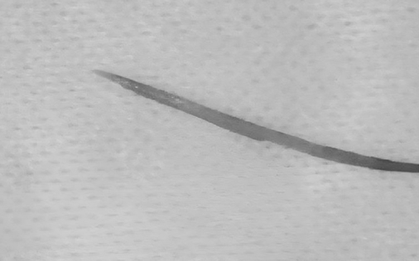

Một người đàn ông 68 tuổi ở Hà Nội may mắn thoát khỏi nguy kịch sau khi nuốt phải thứ quen thuộc dài gần 7cm. Các bác sĩ nhanh chóng gắp ra "sát thủ thầm lặng" rất may không đe dọa tính mạng.